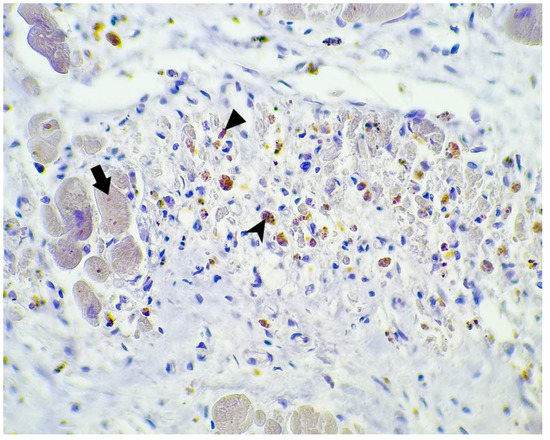

3.2. Immunohistochemical Study